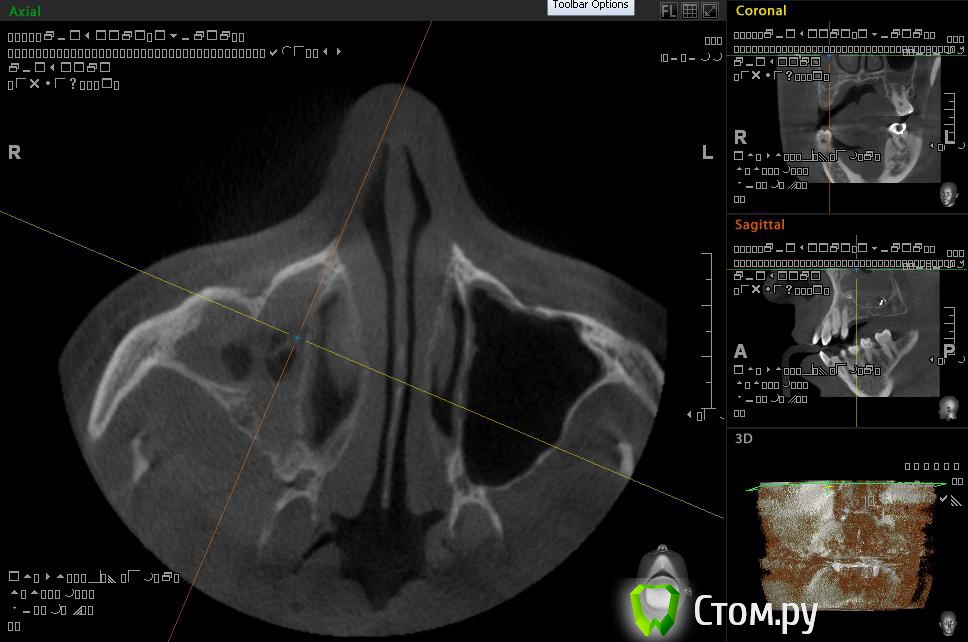

Евений Опубликовано 22 ноября, 2013 Поделиться Опубликовано 22 ноября, 2013 (изменено) Здравствуйте!В 2011 году делал КТ. Заполнена тотально правая пазуха, у медиальной стенки инородное тело овоидной формы, в центре которого объект металлической плотности, мелкие объекты на нижней стенке пазухи. Полипы у носового хода.После этого была радикальная гайморотомия на правой пазухе. Обнаружили застарелый хронический процесс, творожистые массы, поставили холеастому. Гистология операционного материала показала наличие грибка.По своей инициативе сделал 3d-томографию на picasso trio.Рентгенолог сказал про уровень в пазухе и инородное тело.КТ делал во время простуды, был насморк.Сходил на консультацию к профессору, который меня оперировал. Внимательно осмотрев носовую полость он ничего не нашел. Про КТ сказал, что это могут быть корни зубов. Пломбировочный материал отрицает, как и перед операцией. На данный момент - простуда, и оперированную пазуху закладывало больше чем здоровую. Выделения прозрачные, потом желтые и оранжевые.. Из минусов, как и раньше стекает слизь по задней стенке. Вопрос такого плана: Что за загогулины в правой оперированной пазухе? Целесообразно ли делать микрогайморотомию после радикальной, или если будут делать то опять радикальную?Спрашиваю потому, что уже не знаю к кому обращаться у нас в Архангельске. Вроде, операция радикальная была под контролем эндоскопа, уж должны были всё проверить и достать. Делал операцию академик, светило медицины в области хирургической стоматологии и онкологии.И еще - а стоит ли вообще делать вторую операцию? Возможно вред от вмешательства и наркоза перетянет пользу операции. Спасибо!ССЫЛКА НА РЕЗУЛЬТАТЫ ПИКАССО ТРИО http://dfiles.ru/files/qc62dn476 Изменено 22 ноября, 2013 пользователем Евений Ссылка на комментарий

АнтонТЛТ Опубликовано 22 ноября, 2013 Поделиться Опубликовано 22 ноября, 2013 Найдите хорошего ЛОРа, который нормально уберет остатки пломбировочного материала 2 Ссылка на комментарий